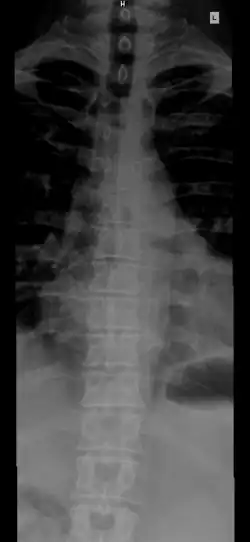

Позвоно́чный столб, или позвоно́чник (лат. columna vertebralis) — основная часть осевого скелета человека. Состоит из 32—33 позвонков, последовательно соединённых друг с другом в вертикальном положении[1][2]. Позвонки разделяют на отдельные типы: шейные, грудные, поясничные, крестцовые (срастаются в крестец) и копчиковые.

Различают 5 отделов позвоночника:

- Шейный отдел (7 позвонков, C1—C7);

- Грудной отдел (12 позвонков, Th1—Th12);

- Поясничный отдел (5 позвонков, L1—L5);

- Крестцовый отдел (5 позвонков);

- Копчиковый отдел (3-4 позвонков)[2], иногда до 5).

Есть 2 вида изгиба позвоночника: лордоз и кифоз. Лордоз — это те части позвоночника, которые выгнуты вентрально (вперед) — шейный и поясничный. Кифоз — это те части позвоночника, которые выгнуты дорсально (назад) — грудной и крестцовый.